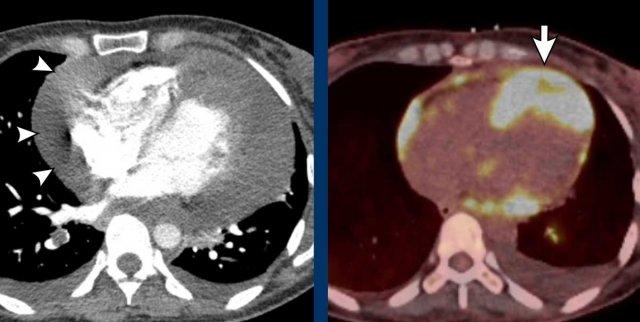

Hình ảnh

Sau nhồi máu cơ tim trong vùng tưới máu của LAD với hình thành phình vùng mỏm, vôi hóa thành và huyết khối trong buồng thất lớn.